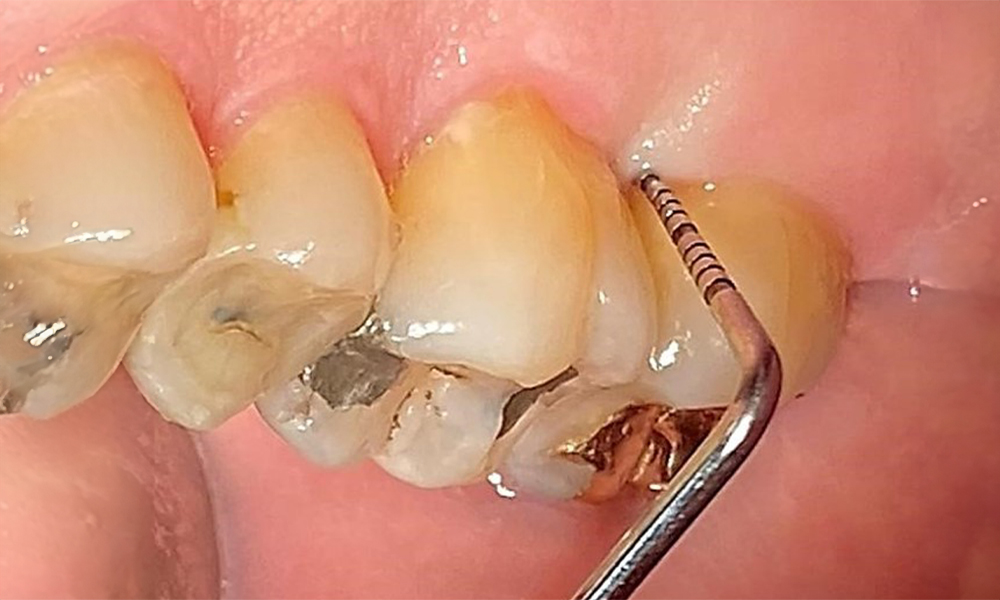

The patient has a full dentition with 28 teeth, which includes amalgam and composite fillings in the molar and premolar regions. There is a visible clinical marginal gap present on tooth 14. Tooth 27 has an adequate gold inlay. There are also generalized attritions and abrasions. (Fig. 2, Fig. 3, Fig. 4, Fig. 5, Fig. 6)

Periodontal findings

The patient has stage II, grade B periodontitis (5). At 1 to 3 mm, the clinical probing depths were within the physiological range. Localized probing depths of 5 mm were observed on the mesiopalatal aspects on both 17 and 27. There are generalized recessions of 1–3 mm with partial loss of the interdental papillae (Fig. 2, Fig. 3, Fig. 4)